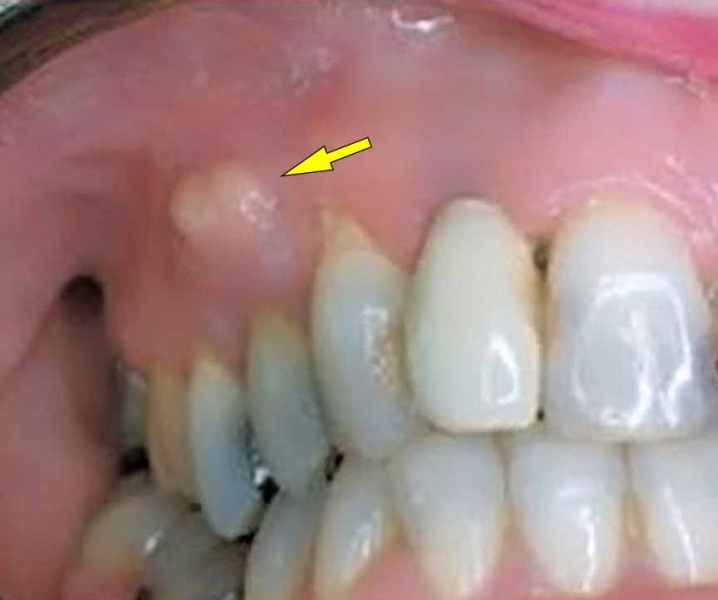

If the required microbes are not available upon the resolution of the conflict, the additional cells remain. Eventually, the growth becomes encapsulated with connective tissue. In conventional medicine, this is usually diagnosed as a mouth polyp or “benign cancer”. A gum polyp might reach into the neck of a tooth.

In the nasopharynx, adenoids or nasal polyps that developed during the conflict-active phase are removed with the help of fungi or TB bacteria, provided they are available. The nasal discharge consists of smelly tubercular secretion. A nasal abscess with painful swelling containing pus also develops in the healing phase.